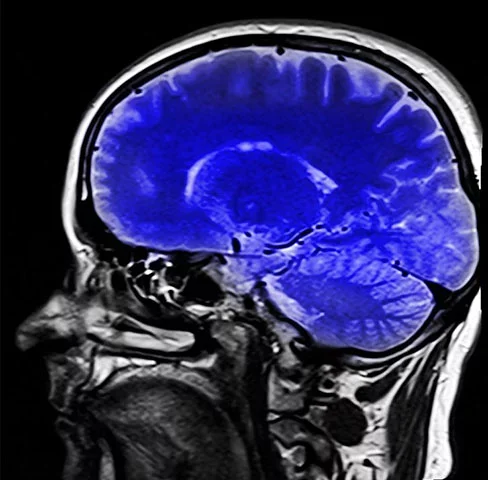

A demência frontotemporal (DFT) é uma doença neurodegenerativa que afeta regiões do cérebro e provoca perda progressiva de funções do órgão. Foto: Tânia Rêgo/Agência Brasil -

Os lobos frontais e temporais laterais são as áreas cerebrais mais afetadas.A DFT é uma condição mais rara que outros tipos de demência e a hereditariedade é um fator muito influente. Foto: - Dominio Publico/hippopx.com -

Além da avaliação dos sintomas, o diagnóstico requer exames complementares. Entre eles, tomografia e ressonância magnética. Foto: Imagem de WikiImages por Pixabay -